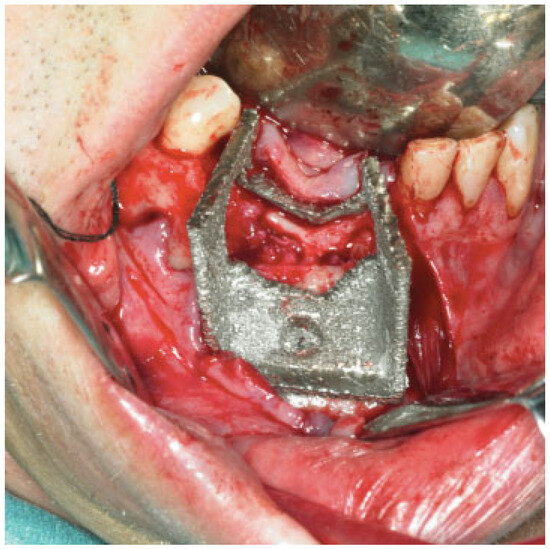

The saw guide was used in the operating theater, checked against the mandible (Figure 4), and then used to perform the planned osteotomies.

During the operations, plates were applied on the segmented fibula flaps and screw fixated with standard titanium nonlocking screws (Synthes®, Switzerland). The titanium mesh was tried for fit after the planned osteotomies were performed.

The additive manufacturing method EBM produces custom-designed implants fully usable under clinical conditions in reconstruction of acquired defects in the mandible with good agreement between the treatment plan and the fit as demonstrated during operation (Figure 4 and Figure 5) and the subsequent short-term clinical as well as the superimposed preoperative treatment plan with the radiological outcome (Figure 6). Clinically, the custom-made cutting guide, mesh, and the load-bearing reconstruction plates were appreciated during surgery as the implants were easy to handle, fixate, and reduced operating time significantly.

Figure 3. The saw guide was checked against the patient mandible.